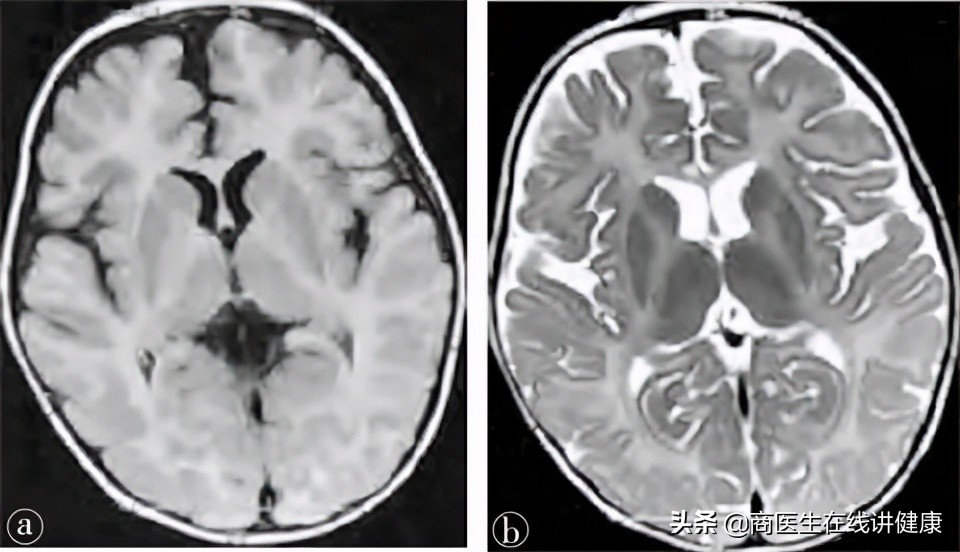

头 颅 核 磁 共 振 图 像(MRI) : 上图为MRI的影像学,而PMD主要影像学通常可以观察到患者的髓鞘发育不良或完全无发育。

PMD患者的头颅MRI影像会显示髓鞘化异常,其异常主要表现在Flair 像弥漫性高信号和脑白质T2 加权像 ,通常通过这两个异常表现来诊断患者是否为PMD患者,因此,MRI对 PMD 诊断具有重要的临床意义。